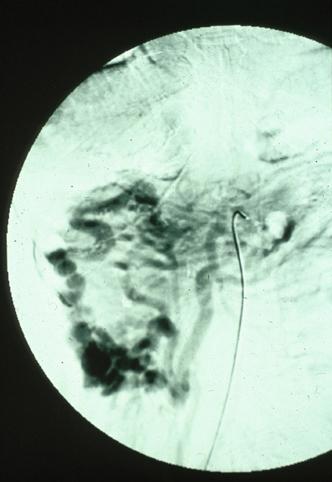

Várices del Colon Ascendente en el que fue de utilidad el estudio angiográfico, que mostró figura de tumor submucoso (Presentado por el Dr. Kawamoto de la Sociedad Gastrointestinal de la Universidad de Kyushu)

Fukuoka Pref., Centro Kyushu de Curaciones de Cáncer (Dr.川元)

Enfermedad Inflamatoria - Ulcerativa/otros

colon/ascendente

Rayos X

40 -